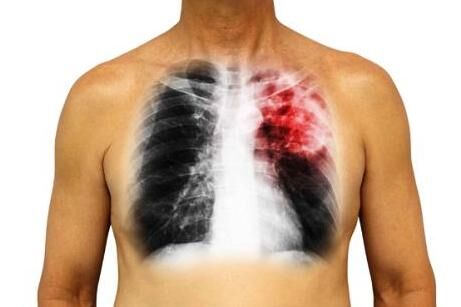

胸痛,呼吸不畅,医生:有这5种不易察觉的征兆,怕是离肺癌不远了

之所以会在很晚的阶段才发现肺癌的情况,是由于在肺癌早期的时候,症状可能并不明显,一些征兆较为常见,因此十分容易被人们所忽视或和其它疾病混淆,导致没有及时发现肺癌。 若是想要及时判断是否有肺癌发生…